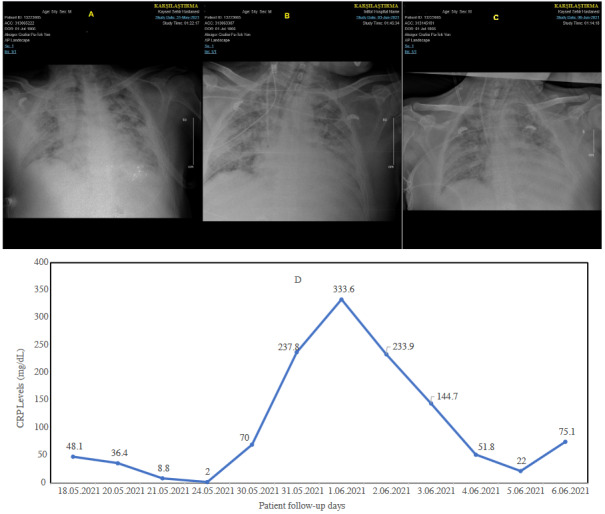

In critical cases, patients complained of respiratory failure (severe dyspnea, shortness of breath > 30/min, tachypnea, hypoxia), fever, reduced blood oxygen saturation of less than or equal to 93%, and pulmonary filtrates, shock, and multiorgan dysfunction, or even failure. Research has also shown that, under severe conditions, patients show signs of impaired breathing, wet rattles, dull percussion, and a decrease in tactile tremor. Apart from respiratory problems, the disease also causes gastrointestinal issues like diarrhea. Laboratory tests of a complete blood count may show an average or reduced white blood count or a reduced lymphocyte count at the beginning of the onset of the disease. Patients also have higher levels of C-reactive protein. The chest CT series and the progression of the CRP of a critical case are illustrated in Figures 2a–2d.

Figure 2.

A sample for critical disease associated with COVID-19. Thoracic CT imaging and CRP course for 51-year-old women COVID19 patient with previously undiagnosed type II diabetes mellitus. A) Thoracic computed tomography at admission. B) Thoracic CT imaging on day eight. C) Thoracic CT imaging on the 37th day. D) Patient’s CRP course. Low-dose tocilizumab (100 mg, 100 mg, every other day at first CRP peak, and 80 mg, and 80 mg one dose at second CRP peak, every other day) four times (a total of 360 mg) and 250 mg three times for 3 consecutive days methylprednisolone and 40 mg/day for 20 days had been administered.